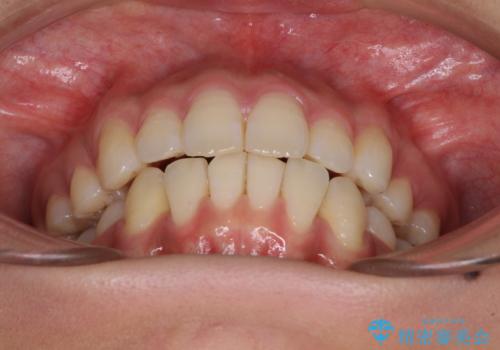

- 以前の矯正治療の後戻りにより、上下の前歯がでこぼこになってしまったことを気にして来院された患者様です。

口元がこれ以上突出することなく前歯の叢生が改善できるよう、歯と歯の間を削ってスペースを獲得し、インビザラインを用いて整えていくこととしました。

目安の装着時間である1日22時間をしっかりと実践してくださり、半年強という短期間で治療を終えることができました。